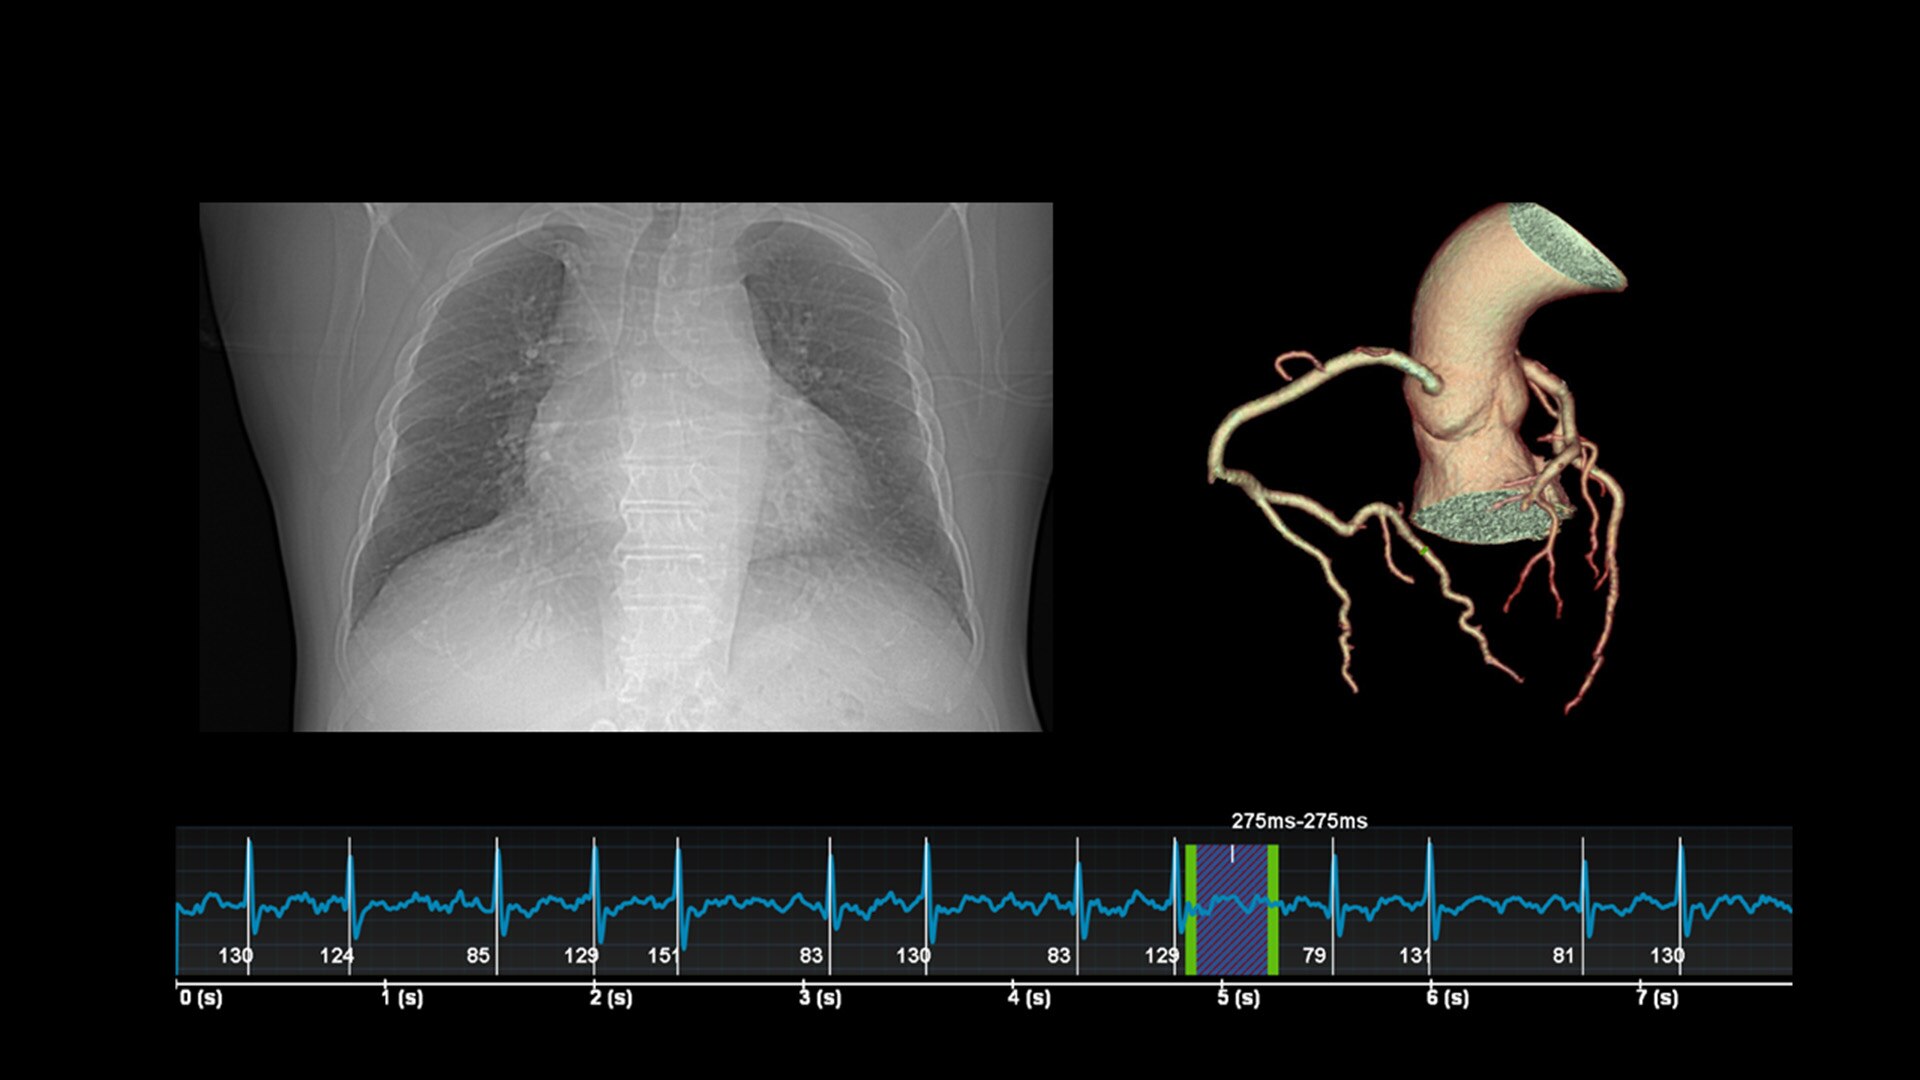

Unlimited 1-Beat Cardiac is designed to provide consistent, high-quality imaging for accurate diagnoses, even in challenging patients with atrial fibrillation, breath-holding difficulties, heavily calcified coronaries, in-stent restenosis, and situations where an ECG trace is unavailable.